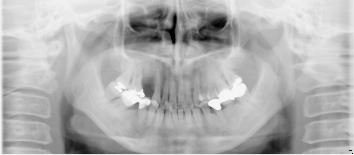

54歳女性

部分義歯がどうしても違和感が強くて、できれば義歯を使わなくてもいいようにしたいとのこと。

下顎はそんなに問題ないですが、上顎は骨の厚みと量、共に乏しく本来はインプラントは不可能です。

あきらめずに、かなり高度な技術ですが骨を増やす手術を併用してなんとか植えることができました。